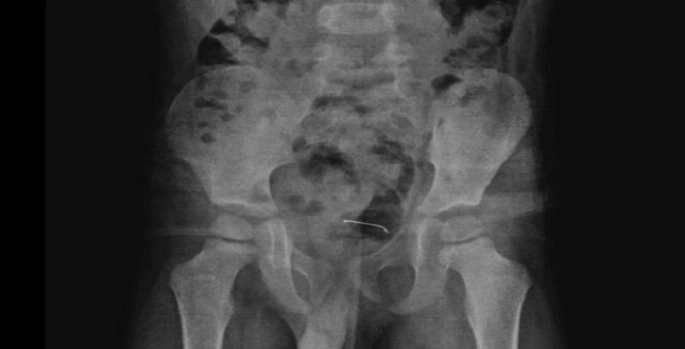

Yapılan röntgen incelemelerinde, mesane duvarında metal bir cisim olduğu tespit edildi. Uzun süre vücutta kalan 3 santimetrelik toplu iğnenin mesane duvarına yapıştığı belirlendi.

Ailenin bilgilendirilmesinin ardından Tatvan Devlet Hastanesi Çocuk Cerrahi Uzmanı Op. Dr. Tahsin Onat Kamçı tarafından gerçekleştirilen operasyonla, toplu iğne başarılı bir şekilde çıkarıldı. Ameliyat sonrası birkaç gün gözlem altında tutulan çocuk, tekrar kontrole gelmek üzere taburcu edildi.

Hastanın kontrollerinde, yuttuğu cismin doğal yollarla vücuttan çıkmadığını tespit ettiklerini anlatan Kamçı, "Bunun üzerine ameliyat kararı aldık. Ameliyatta cismin mesane duvarına yapıştığını gördük. Cerrahi operasyonla 3 santimetre civarındaki toplu iğneyi çıkardık. Hastayı birkaç gün takipte tuttuk. Genel sağlık durumu iyi olan hastamızı taburcu ettik" diye konuştu.